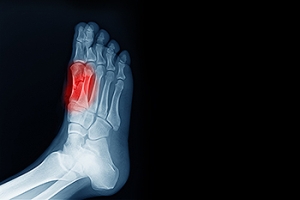

Sesamoiditis is a painful condition that affects two small sesamoid bones located under the big toe joint. It occurs when these bones become irritated or inflamed, usually due to overuse or repetitive pressure from high-impact activities like running or jumping. Symptoms include pain at the base of the big toe, swelling, and tenderness, especially when bearing weight or pushing off during walking or running. The pain from sesamoiditis can feel sharp or throbbing, and it often worsens with activity. Rest and anti-inflammatory medications are common initial treatments. Wearing cushioned footwear or using custom orthotics to reduce pressure on the affected area can also help. In more severe cases, your podiatrist may recommend corticosteroid injections. This type of doctor specializes in diagnosing and treating conditions like sesamoiditis, helping to reduce pain and prevent further damage. If you are experiencing pain near the base of your big toe, it is suggested that you schedule an appointment with a podiatrist for a tailored treatment plan.

Sesamoiditis is a condition of the foot that affects the ball of the foot. It is more common in younger people than it is in older people. It can also occur with people who have begun a new exercise program, since their bodies are adjusting to the new physical regimen. Pain may also be caused by the inflammation of tendons surrounding the bones. It is important to seek treatment in its early stages because if you ignore the pain, this condition can lead to more serious problems such as severe irritation and bone fractures.